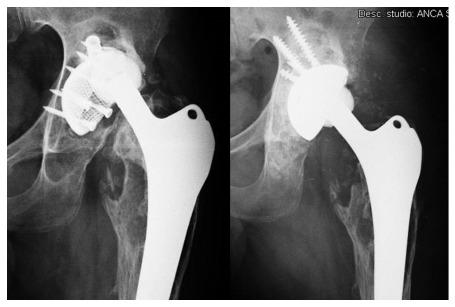

使用多孔钽组件的髋臼翻修术:一项随访5至10年的回顾性研究。

Acetabular revisions using porous tantalum components: A retrospective study with 5-10 years follow-up.

To evaluate the clinical and X-ray results of acetabular components and tantalum augments in prosthetic hip revisions.

Fifty-eight hip prostheses with primary failure of the acetabular component were reviewed with tantalum implants. The clinical records and X-rays of these cases were retrospectively reviewed. Bone defect evaluations were based on preoperative CT scans and classified according to Paprosky criteria of Radiolucent lines and periprosthetic gaps; implant mobilization and osteolysis were evaluated by X-ray. An database was created and statistical analyses were performed with SPSS software (IBM SPSS Statistics for Windows, version 23.0). Statistical analyses were carried out using the Student's test for independent and paired samples. A value of < 0.05 was considered statistically significant and cumulative survival was calculated by the Kaplan-Meier method.

RESULTS

The mean follow-up was 87.6 ± 25.6 mo (range 3-120 mo). 25 cases (43.1%) were classified as minor defects, and 33 cases (56.9%) as major defects. The preoperative HHS rating improved significantly from a mean of 40.7 ± 6.1 (range: 29-53) before revision, to a mean of 85.8 ± 6.1 (range: 70-94) at the end of the follow-up (Student's test for paired samples: < 0.001). Considering HHS only at the end of follow-up, no statistically significant difference was observed between patients with a major or minor defect (Student's test for independent samples: > 0.05). Radiolucent lines were found in 4 implants (6.9%). Postoperative acetabular gaps were observed in 5 hips (8.6%). No signs of implant mobilization or areas of periprosthetic osteolysis were found in the x-rays at the final follow-up. Only 3 implants failed: 1 case of infection and 2 cases of instability. Defined as the end-point, cumulative survival at 10 years was 95% (for all reasons) and 100% for aseptic loosening of the acetabular component.

CONCLUSION

The medium-term use of prosthetic tantalum components in prosthetic hip revisions is safe and effective in a wide variety of acetabular bone defects.